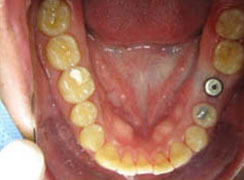

鎖上癒合帽,傷口極小,不需縫合